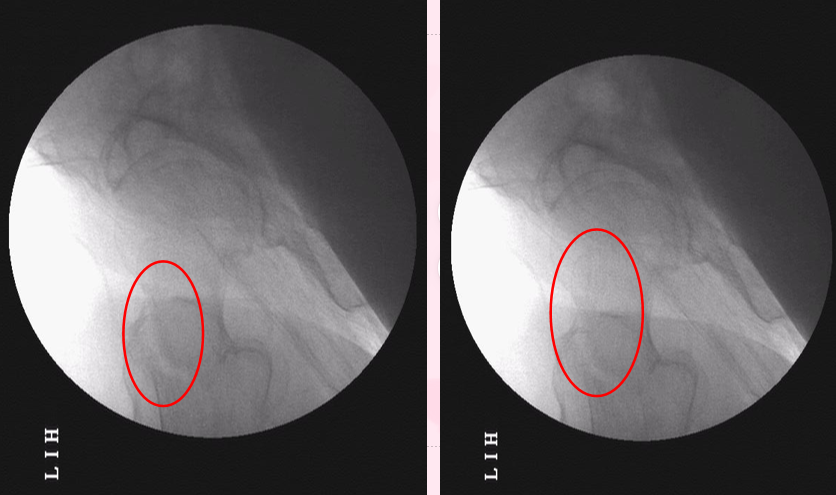

消毒后,手动牵引复位(无牵引床),透视正位可,透侧位前方有分离

1.分离与CT对应处,显示前方分离。2.CT平扫加重建有助于术中复位。

侧位透视下,内旋右下肢,复位逐渐良好。。。一人保持复位内旋位固定(不好意思,因透视快速忘了保存,最后一张完全复位片没留,遗憾)